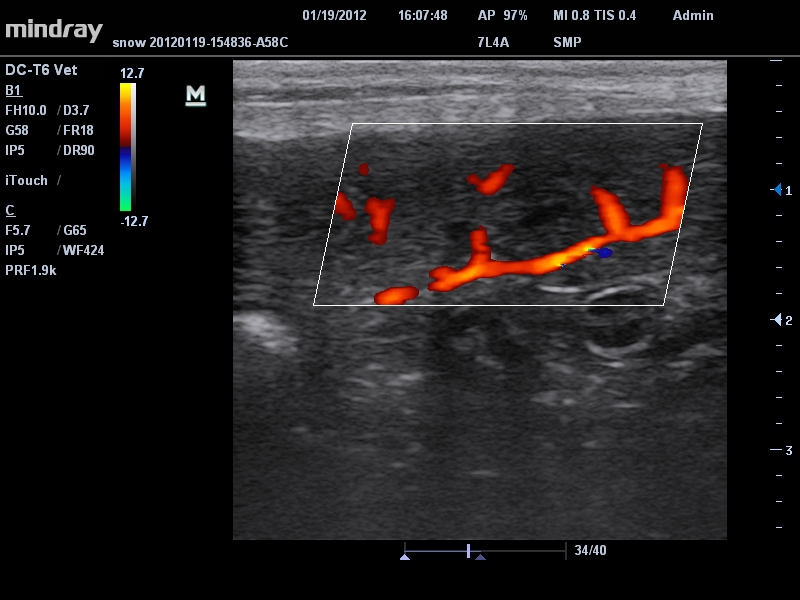

Да

• Режимы сканирования: B/M/CFM/PDI/Направленный PDI/PW, HPRF, Тканевая гармоника, М- и цветной М-режим.

• Линейный ультразвуковой датчик Mindray 7L4A